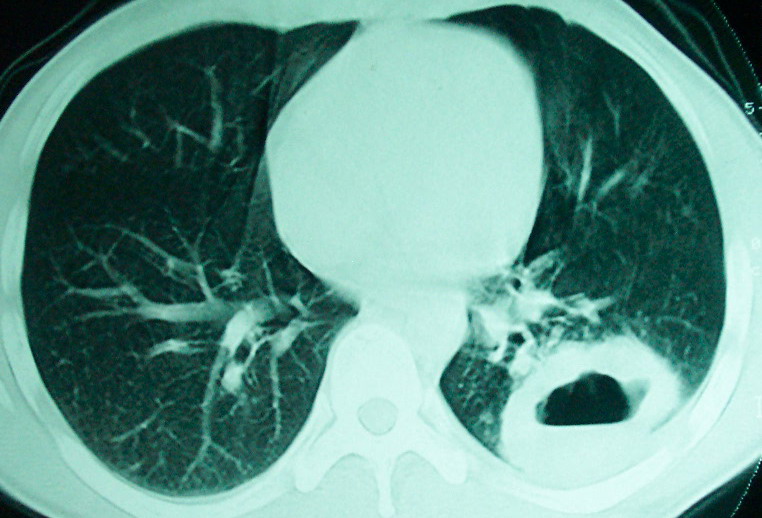

左下肺病灶除了明显的厚壁空洞 气液平外,明显见壁结节,另两肺多发小结节,综合考虑:左下肺周围性肺癌伴肺内转移.

鳞癌肺肺转移:厚壁空洞,洞壁厚薄不均,内似有壁结节,肺脓肿临床有无提示,血像如何?病灶周围很干净,没有明显渗出,很勉强?

空洞内可见小结节样密度影考虑合并真菌感染